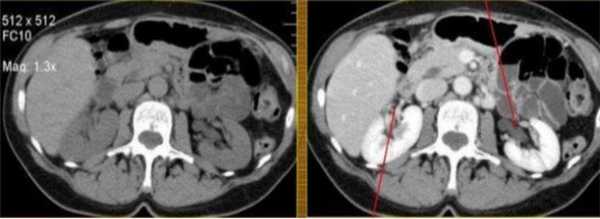

КТ почек без контраста (слева) и с контрастом (справа): стрелками указаны сосуды в воротах почек